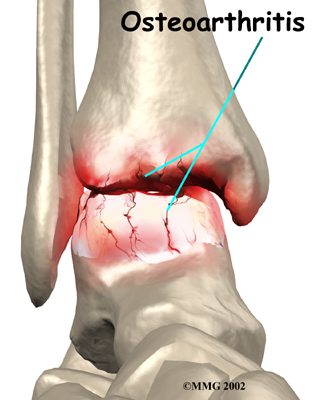

OA is usually considered a type of degenerative arthritis, or wear-and-tear arthritis. Doctors consider OA pretty much the same whether it appears years after an injury to the joint or whether it appears without any history of injury. It behaves more or less the same way.

Injury to a joint, such as a bad sprain or fracture, can cause damage to the articular cartilage. The cartilage can be bruised when too much pressure is exerted on it. This damages the cartilage, although if you look at the surface it may not appear to be any different. The injury to the material doesn't show up until months later. Sometimes the cartilage surface is damaged even more severely, and pieces of the cartilage are ripped from the bone. These pieces do not heal back and usually must be removed from the joint surgically. If not, they may float around in the joint, causing the joint to catch and be painful. These fragments of cartilage may also do more damage to the joint surface.

Once this cartilage is ripped away, it does not normally grow back. Unlike bone, holes in the surface are not simply replaced by the cartilage tissue around the hole. Instead the defects are filled with scar tissue. The scar tissue that forms is not nearly as good a material for covering joint surfaces as the cartilage it replaces. It just can't support weight and isn't smooth like true articular cartilage.

Over many years this imbalance in the joint mechanics can lead to damage to the articular surface. Since articular cartilage cannot heal itself very well, the damage adds up. Finally, the joint is no longer able to compensate for the increasing damage, and it begins to hurt. The damage occurs well before the pain begins.